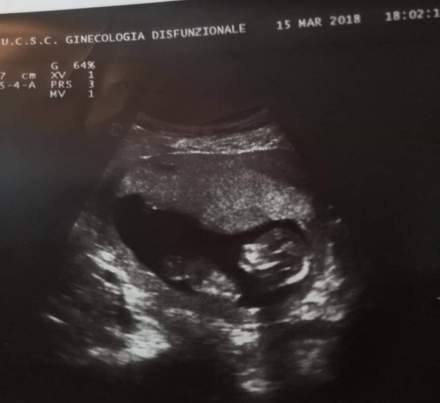

Queste furono le parole del giovane medico che mi visitò quella mattina. Ero incinta di 13 settimane.

Ora vada giù, faccia la linfoscintigrafia per individuare il linfonodo sentinella, poi eco mammaria ed eco ostetrica“. L’ intervento era fissato per le 14.30.

Quando mi fecero l’ ecografia ostetrica la ginecologa mi guardò, avevo gli occhi lucidi. Amavo alla follia quell’esserino millimetrico che cresceva dentro di me. Cresceva lui, ma cresceva pure un nemico silenzioso, che già stava mettendo per bene le sue radici. La dottoressa stampò la foto del mio piccolo e mi disse:”Questa sarà la tua forza. Tienilo con te sul comodino“. Così feci. Ero digiuna dal giorno prima e sul comodino avevo solo una Corona del Rosario e la foto del mio scricciolo. La mattinata trascorse tra messaggi su WhatsApp e preghiera. Tanta preghiera. Ringraziavo e lodavo Dio anche per quella situazione. Non avevo paura. Ero in buone mani. Dal momento del test di gravidanza positivo sapevo che Dio mi stava donando una seconda possibilità.

Ps. Guardate un po’ la perfezione del mio piccolo “grumo di cellule” a 13 settimane di gestazione. Sarei voluta morire io piuttosto che sacrificare la sua di vita.